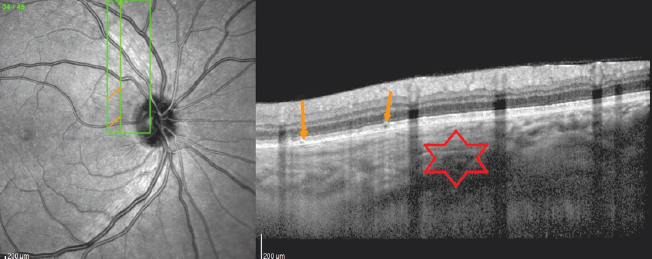

In all cases, the outer border of the choroid was clearly identified during the OCT examinations. In fact, two tomographic patterns were revealed that had large foci.

- The presence of an elavated choroidal complex with a mesh structure at the level of the outer layers of the choroid and hyperreflective line separating the tumor from the intact sharply thinned choroid in combination with single local hyperreflective foci at the RPE level (Fig. 9). These zones corresponded to calcified CO [5, 30].

Fig. 9. Optical coherence tomography of the patient N. (35 years old). Circular scan of the peripapillary area. Green arrows – hyperreflective line separating choroidal osteoma from the thinned choroid; orange arrows – zone of impaired Bruch’s membrane visualization; asterix – choroid with a “mesh structure”; red arrows – a zone of the dramatic choroidal thinning. Fundus photo – Fig. 7

Рис. 9. Оптическая когерентная томография левого глаза пациентки Н., 35 лет; круговой скан через перипапиллярную зону. Зелёные стрелки — гиперрефлективная линия, отделяющая остеому хориоидеи от истончённой хориоидеи; оранжевые стрелки — зона нарушения визуализации мембраны Бруха; звёздочка — зона хориоидеи с сетчатой структурой; красные стрелки — зона резкого истончения хориоидеи. Фото глазного дна — см. рис. 7

- The presence of a moderately hyperreflective zone of the choroid elevation with a lamellar structure of the choroid complex in the absence of changes in the retina located above, which corresponded to decalcified CO (Fig. 10) [30, 31]. The CO decalcification also resulted to choroid atrophy (Fig. 9) [30].